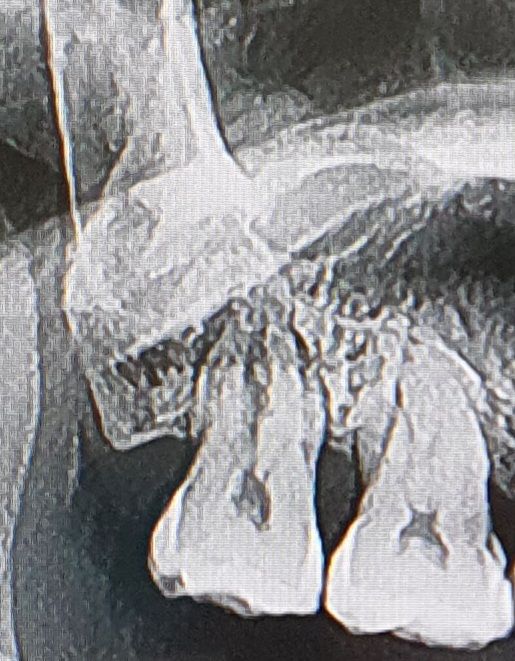

아래쪽 치아 발치하다가 위쪽맨끝어금니 발치기구에 부딪혔던 치아입니다.

부딪히고나서 2주후에 치간칫솔에 찔려서 그런건지 잇몸염증으로 병원에 갔을때 찍은 사진입니다.

오른쪽 두번째 어금니 20년째 치료받고 흔들리지만 발치얘기가 없는데 발치기구에 부딪힌 맨끝 어금니 그뒤로 흔들리고 해서 발치해야 된다고 하는데 발치하는게 맞는건가요!?

금이 가거나 한것은 없는지 살펴봐주시면 감사하겠습니다.